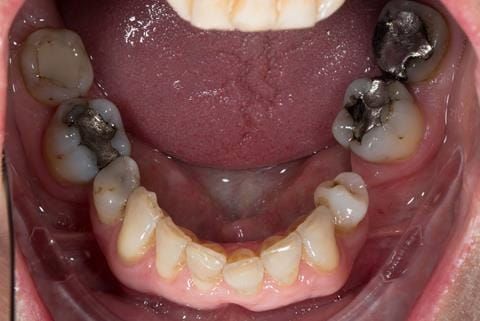

- Other than the maxillary incisors the remaining dentition was in marginally better condition being moderately to heavily restored. Many will probably require replacement and restoration from time to time mainly from wear and tear owing to occlusal forces.

- Extract the upper 2-2 teeth and replace with an interim acrylic based partial denture. Reline the interim denture over 9 - 12 months, replacing with a definitive cobalt chromium based partial denture. The definitive denture would ideally be designed as an occlusal protective splint to reduce the the potential for mechanical wear and breakages of the moderately/heavily restored maxillary dentition. In addition, should further upper teeth require extraction they could be added on to the denture cobalt chromium framework - therefore a new prosthesis would not be required as future teeth are lost. This option would produce an excellent aesthetic outcome. This is the option the patient chose to have.